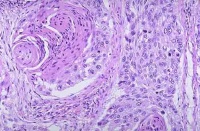

表皮角化,肿瘤由鳞状上皮细胞团块所组成,不规则地向真皮内浸润,棘细胞呈瘤性增生,呈条索状或巢状细胞团,边缘以基底细胞层,中心部有角化性癌珠,在癌细胞团内有很多分裂象,周围淋巴细胞和浆细胞浸润。

鳞状细胞癌可表现角化、角化珠形成和/或细胞间桥等特征。这些特征随分化程度而表现不同。在分化良好的肿瘤中该特征表现明显,而在分化差的肿瘤中仅局部可见。

鳞状细胞癌

乳头状型SCC。一些位于近端支气管的肿瘤可表现向外生长和支气管内生长。有时仅可见非常局限的上皮内扩散不伴有浸润,但是大多数病例中存在浸润形成。